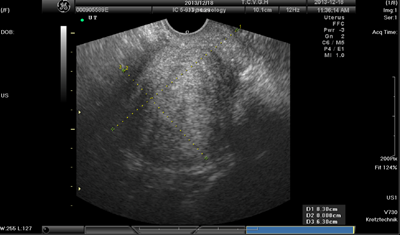

Her ultrasound exanimation performed at admission revealed the size of the uterus as 102x59x63mm. The ultrasound graph is shown in Figure 1. The value of serum CA-125 level, menstrual bleeding according to the scoring method15,16 and menstrual pain on the visual analogue scale (VAS) of 0 to 1016 are shown in Figure 2. The symptoms were very severe, and fertility was no longer a consideration to the patient. The physician strongly suggested a hysterectomy. The patient was an experienced meditation practitioner, and has learned meditation at a Buddhist center in Taiwan from a teacher with the knowledge of Tibetan Buddhism. She consulted her teacher and then decided to try meditation before hysterectomy. The methods she used (intervention I), described in a qualitative interview, were to identify her greatest stressor at that time and then let go of it, followed by the intensive practice of mantra meditation and mindfulness meditation, for approximately 1.5hours per day and approximately 10hours per week, while taking anti-inflammatory, hemostatic drugs, iron and vitamin B supplements as necessary. After over 1month of this treatment regimen, serum CA-125 level, menstrual pain, and menstrual bleeding were reduced considerably, as depicted in Figure 2. Because of the alleviation of symptoms, no hysterectomy or any other operation was performed on her.